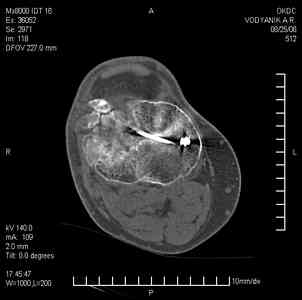

Уважаемые коллеги,В ортопедическое отделение обратился пациент: мужчина 47 лет, который в течение 4-х лет дваждыполучил травму костей, образующих правый коленный сустав. В 2002 v внутрисуставной оскольчатыйперелом проксимального метаэпифиза правой большеберцовой кости; в 2005 v внутрисуставнойоскольчатый перелом дистального метаэпифиза правой бедренной кости. В обоих случаях в разных лечебных учреждениях проводилось оперативное лечение переломов.При осмотре в отделении на основании результатов клинического осмотра и данных визуальныхметодов обследования поставлен диагноз:тугой ложный сустав дистальной трети правой бедренной кости, состояние после накостногоостеосинтеза перелома типа 33-В2.2 ; несросшийся перелом надколенника; неправильно сросшийсяперелом латерального мыщелка правой большеберцовой кости, состояние после металлоостеосинтезаперелома 41-В2.2; сочетанная осевая деформация правой ноги: варусная деформация правого бедра,вальгусная деформация правой голени; посттравматический артроз коленного сустава 4 ст по Kellgren-Lowrence; выраженное нарушение функции ходьбы и опоры. Внешний вид ноги больного, данные рентгенографического обследования и избирательно выделенные компьютерные томограммы приведены в приложении. В именах КТ использовано кодирование уровня по АО, т.е. _41, например, означает проксимальную треть голени.В отделении намечен v очень предварительно v следующий план лечения: 1. Иметь ввиду перспективу тотального эндопротезирования коленного сустава. 2. С учетом п.1 при проведении действий, направленных на устранение ложного сустава бедренной кости не использовать материалы, не подвергающиеся трансформации. 3. В ходе операции, направленной на устранение ложного сустава: А. удалить все металлоконструкции; Б. ревизовать зону пролежня под пластиной на бедре, при наличии признаков достаточной жизнеспособности кости выполнить остеопериостальную декортикацию, дрилинг ложа пластины; В. Удалить рубцовую ткань по плоскости ложного сустава, и в пространстве между костными форагментами, насечь обращенные друг к другу поверхности. Ввести штифт с блокированием (например Stryker с учетом особенностей расположения дистальных блокирующих винтов у этойконструкции). Осуществить остеосинтез с учтанением варусной деформации бедренной кости. Пространство в зоне ложного сустава и пустоты в метафизе бедренной кости заполнить резорбирующимся цементом на основе гидроксиапатита кальция. Для дистальной фиксации использовать винты с переменным шагом резьбы. Вариант:, винты вводить после заполнения метафиза цементом. Дополнительные виды создания межфрагментарной компрессии во встречно-боковом направлении обсуждаются. Г. Быть готовым к кровопотере. Д. Учесть высокий риск инфекции, тромбоэмболических осложнений. Е. Вопрос о внешней иммобилизации решить по результатам оценки стабильности остеосинтеза. Вариант - одноосевой стержневой аппарат для шунтирования гвоздя с модулем на голени и дистракцией коленного сустава в течение 3-5 недель. Просим вашей критики намеченного плана и конструктивных предложений. С уважением к сообществу, Ординатор В.С. Саплин

Движения приличные, есть за что бороться. Такая ротация голени кнаружи, если она действительно есть (для уточнения можно сделать КТ на уровне обоих метафизов и бедреных, и берцовых ксотей, не меняя положение ног во время съемки), большого значения не имеет. А уж на фоне всего остального тут - вообще говорить не о чем.